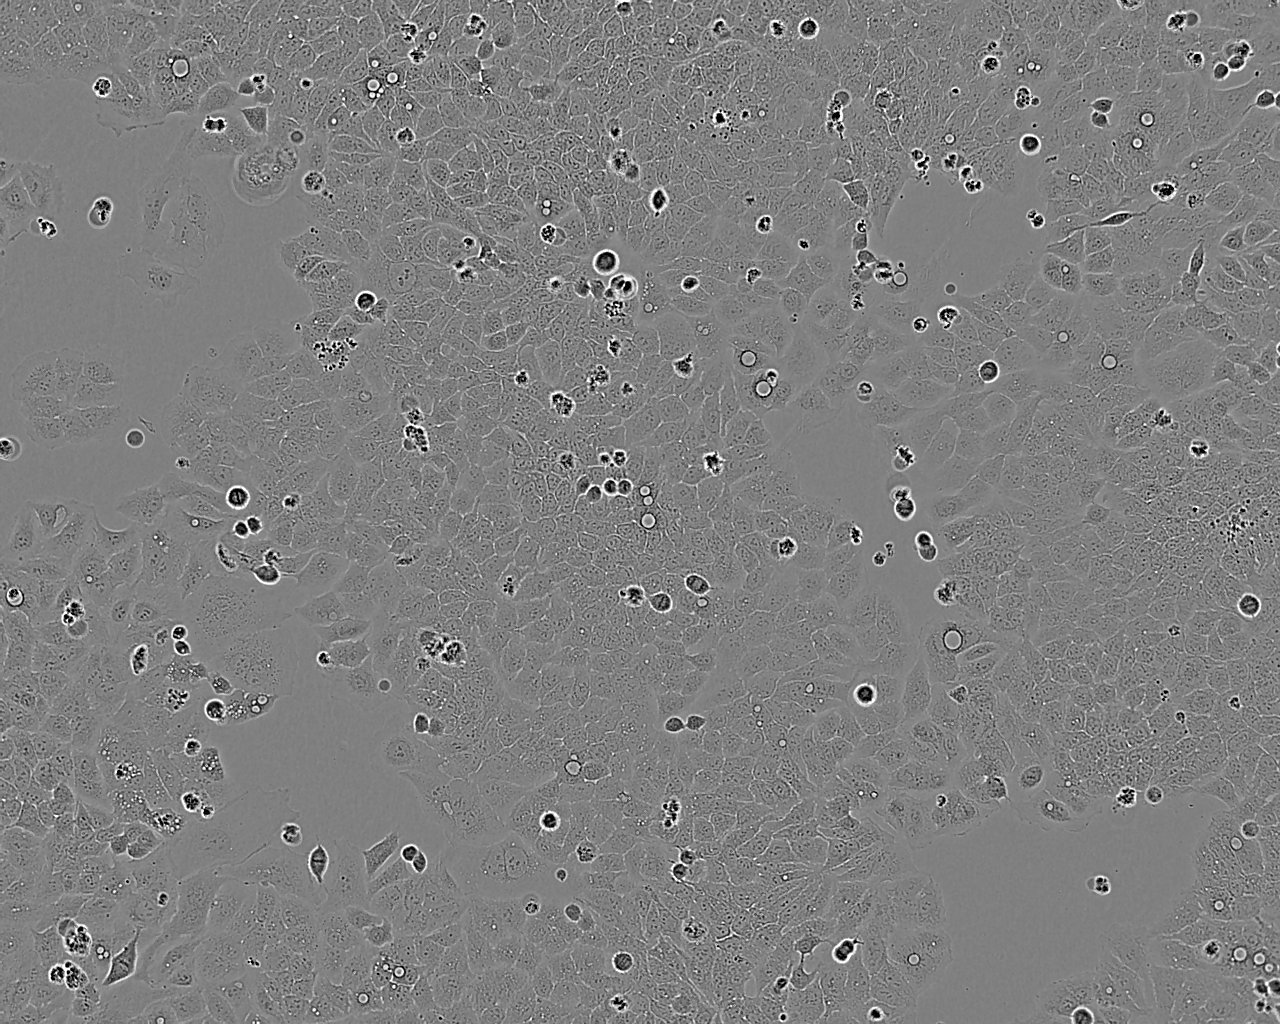

OCM-1 cell line人眼脉络膜黑色素瘤细胞系

OCM-1 cell line

细胞背景资料:葡萄膜黑色素瘤;女性

细胞形态:上皮细胞样

细胞生长:贴壁

细胞生长特性:贴壁